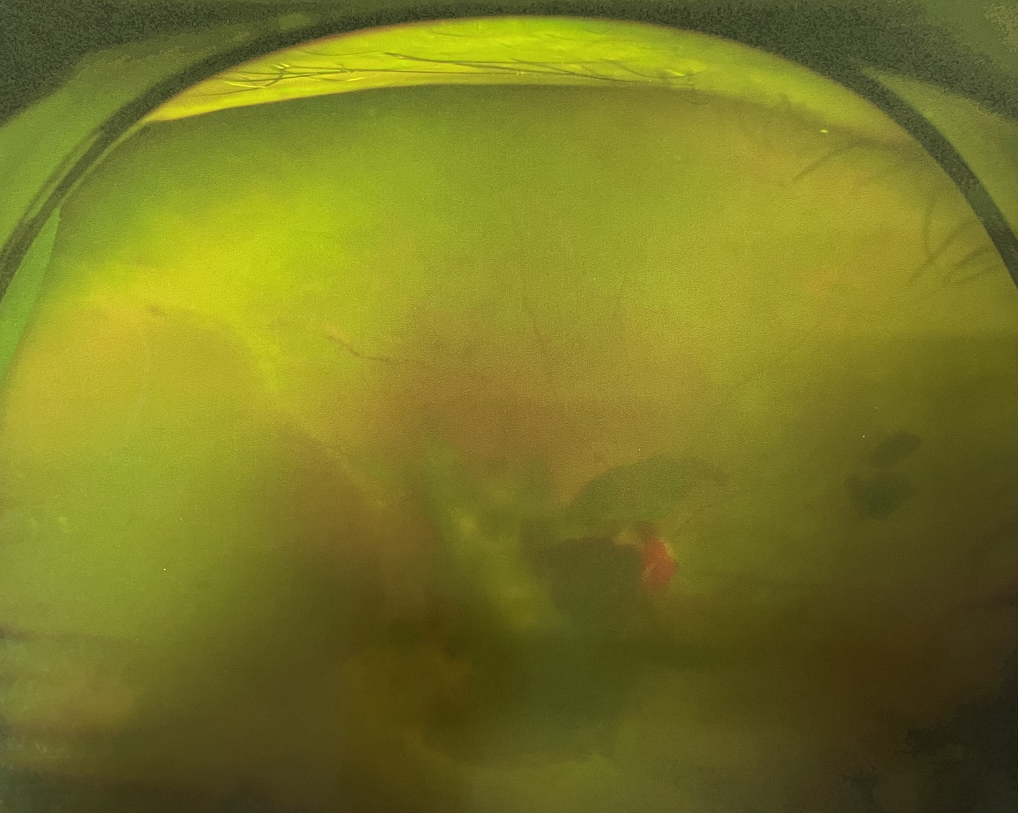

眼底出血多指玻璃體內(nèi),眼睛更深處的視網(wǎng)膜出血。通常情況下,肉眼難以發(fā)現(xiàn)眼底出血,而且發(fā)病初期眼睛也無明顯癥狀,只有借助專業(yè)的眼底檢查儀器才能觀察到異樣。那么眼底出血嚴(yán)重嗎?

誘發(fā)眼底出血的原因眾多,常見的有全身性血管病和血液病、視網(wǎng)膜血管異常、機(jī)械性阻塞、炎癥性疾病或免疫復(fù)合物侵犯血管壁等。

眼底出血嚴(yán)重嗎?其中,“三高”患者、高度近視患者和滲出性或濕性老年黃斑變性患者是眼底出血的高發(fā)人群。

醫(yī)生提醒,一旦眼睛出現(xiàn)視力下降、視物變形、視野缺損或眼前有黑影等視覺“異常”的情況,應(yīng)及時到醫(yī)院進(jìn)行眼底檢查,及早發(fā)現(xiàn),及早治療,以免貽誤病情。

眼底出血嚴(yán)重嗎?對于已出現(xiàn)黃斑水腫、視網(wǎng)膜新生血管的患者,根據(jù)眼底血管造影、oct等檢查結(jié)果,給予玻璃體腔注射抗VEGF藥物及激光治療,可以減輕黃斑水腫,使視網(wǎng)膜新生血管消退,以免進(jìn)一步發(fā)生玻璃體出血、視網(wǎng)膜脫離等嚴(yán)重并發(fā)癥的出現(xiàn)。對于玻璃體出血者,傳統(tǒng)認(rèn)為玻璃體出血3-6個月不吸收再進(jìn)行手術(shù)干預(yù),但近年來因?yàn)轱@微手術(shù)設(shè)備及玻璃體切割技術(shù)已非常成熟,故對于1個月不吸收的玻璃體出血者就可以考慮手術(shù),即手術(shù)時機(jī)應(yīng)該具體情況具體分析,因人而異。